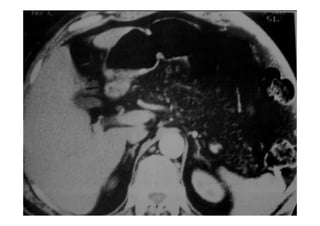

ANATOMIA VASCULAR

A V.PORTA(VP) FORNECE 70% DO SANGUE QUE CHEGA NO FÍGADO E

SE ORIGINA POSTERIOR AO COLO DO PÂNCREAS DA

CONFLUÊNCIA DAS VEIAS MESENTÉRICA SUPERIOR E ESPLÊNICA.

NO HILO HEPÁTICO A VP DIVIDE

NO HILO HEPÁTICO A VP DIVIDE-

-SE EM VPD E VPE.

SE EM VPD E VPE.

A A.HEPÁTICA FORNECE 30% DO SANGUE PARA O FÍGADO E 50%

DO OXIGENIO DISPONÍVEL.

GERALMENTE ORIGINA

GERALMENTE ORIGINA-

-SE DE UM RAMO DO TRONCO

SE DE UM RAMO DO TRONCO

CELÍACO(AGE+AH+AE)

NO HILO HEPÁTICO DIVIDE

NO HILO HEPÁTICO DIVIDE-

-SE EM RAMO DIREITO E ESQUERDO.

SE EM RAMO DIREITO E ESQUERDO.

AS VV. HEPÁTICAS DRENAM PARA A VCI.AS TRÊS VEIAS HEPÁTICAS

(DIREITA, MÉDIA E ESQUERDA) SITUAM

(DIREITA, MÉDIA E ESQUERDA) SITUAM-

-SE PÓSTERO

SE PÓSTERO-

-SUPERIOR

SUPERIOR

AO FÍGADO E DRENAM PARA VCI LOGO ABAIXO DO DIAFRAGMA.